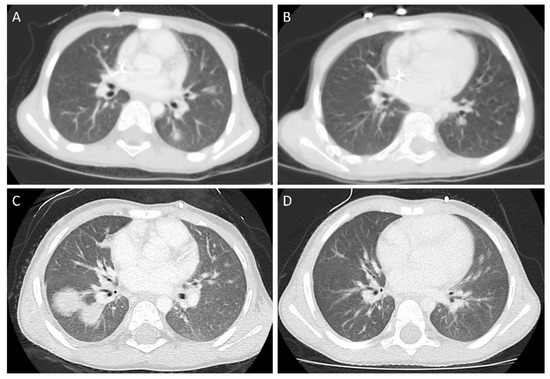

In our center (Department of Pediatrics, Oncology and Hematology, Medical University of Lodz, Poland), the patients with high-risk neuroblastoma are treated according to the subsequent versions of European HR-NBL/SIOPEN (High-Risk Neuroblastoma /International Society of Paediatric Oncology Europe Neuroblastoma) Protocols. In the decade between 2010–2019, we treated, in total, 21 patients with high-risk neuroblastoma. For MAT/SCT (meyloablative chemotherapy /stem cell transplantation), the patients are referred to the Department of Pediatric Bone Marrow Transplantation, Oncology, and Hematology, Wroclaw Medical University, Wroclaw, Poland, which is the most active pediatric BMT (bone marrow transplantation) unit in our country. In two male patients, separated by an interval of 3.5 years, both coming from rural areas with history of pet exposure, in planned imaging studies performed in the first case after induction of rapid COJEC (cisplatin, vincristine, carboplatin, etoposide, and cyclophosphamide) therapy and before tumor resection (Patient 1), and in the second case (Patient 2) after MAT/SCT (42 days post SCT), we found focal lesions in the lungs. Pulmonary recurrence/metastases were strongly suspected, and the representative computed tomography (CT) scans are presented in Figure 1. Both patients were apparently asymptomatic at that time. Surprisingly, in both cases, scintigraphy was negative for pathological 123I mIBG uptake in the chest, suggesting no active disease in the lungs. In one case (Patient 2), we proceeded to surgical biopsy, with the histopathological examination demonstrating no neoplastic tissue, whereas in the other patient (Patient 1), the biopsy was not plausible anatomically. As in both patients there was a marked eosinophilia in the peripheral blood, and there are descriptions of toxocariasis in children treated for high-risk neuroblastoma [4], we also performed serological studies for toxocariasis, and the serology was positive in both patients. The details of treatment and diagnostics of both patients are summarized in Table 1. We initiated toxocariasis treatment with albendazole in both patients with variable success. Patient 1 had features of relapsing infestation. He received two courses of albendazole prior to MAT/SCT and was free from signs of toxocariasis, though with positive serology, while MAT was initiated. He was not tested for T. canis and there was no hypereosinophilia during the hospitalization post SCT in the BMT Unit. Following full hematopoietic reconstitution, while there were no abnormal radiological findings in the lungs, we observed a relapse of hypereosinophilia (reaching a maximal value of 9.500 /µL) and skin rash around four weeks post SCT. He was again treated with albendazole, with no improvement in laboratory markers of toxocariasis, and eventually the patient was switched to diethylcarbamazine (especially in light of scheduled potentially associated with adverse events in anti-GD2 immunotherapy). His eosinophil count was finally normal following two courses of diethylcarbamazine, and there were no features of toxocariasis recurrence later during treatment and follow-up. Patient 2 responded favorably to the second course of albendazole following relapse of hypereosinophilia two months post first albendazole therapy. Figure 1 demonstrates the lesions found in initial imaging (lung CT) after autoSCT and the resolution of changes following anti-parasitic treatment. In both patients, we proceeded with further treatment according to the HR NBL/SIOPEN Protocols, as presented in Table 1.

Figure 1. Pulmonary lesion pre- (A,C) and post- (B,D) antiparasitic treatment in Patient 1 (A,B) and Patient 2 (C,D). A: left lung, inferior lobe, segment 6. C: right lung, inferior lobe, segments 6, 8, 10.